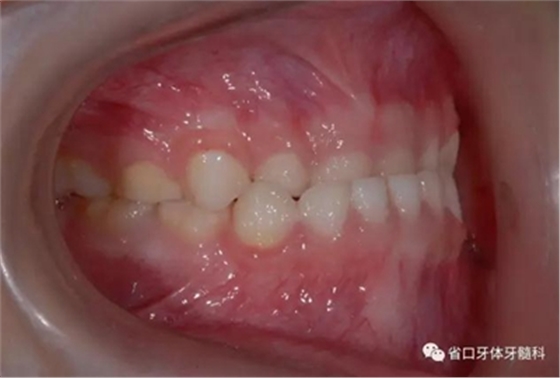

圖6 右側(cè)45度牙相